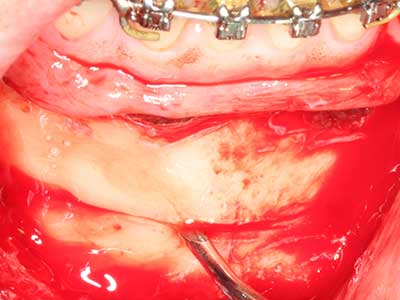

Die Präparation des lateralen Fensters bei der externen Sinusbodenelevation stellt gerade für chirurgisch unerfahrene Implantologen eine große Herausforderung dar. Die knöcherne Bedeckung der Kieferhöhle ohne eine Verletzung der darunterliegenden Schneider’schen Membran abzutragen ist dabei nur ein Teil der Operation – nach Schaffung eines ausreichenden Zugangs muss die Kieferhöhlenschleimhaut vorsichtig mobilisiert werden, um Raum für das einzubringende Material bzw. die Implantate zu schaffen. In dieser Indikation ist die Piezochirurgie zweierlei hilfreich: zum einen kann durch Verwendung diamantierter Instrumente eine selektive Knochenabtragung erfolgen und die darunter liegende Schleimhaut bleibt bei vorsichtiger Vorgehensweise intakt. Zum anderen unterstützen die Ultraschallfrequenzen zusätzlich eine komplikationslose Ablösung der Schleimhaut – sie werden durch spezielle stumpfe Ansätze in den Spaltraum zwischen Schleimhaut und Kieferhöhlenboden übertragen (Cassetta, Ricci et al. 2012, Pereira, Gealh et al. 2014) (Rickert, Vissink et al. 2013). So erscheint es nicht verwunderlich, dass in aktuellen Übersichtsarbeiten über die externe Sinusbodenelevation neben der Verwendung von rauen Implantatoberflächen und dem Einsatz von Knochenersatzmaterialien auch der Einsatz von piezoelektronischen Geräten als positiv bewertet wird (Wallace, Tarnow et al. 2012).